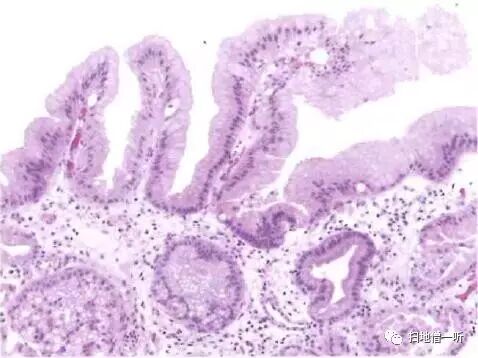

病理组织学可见腺窝上皮增生性变化,腺管囊状扩张